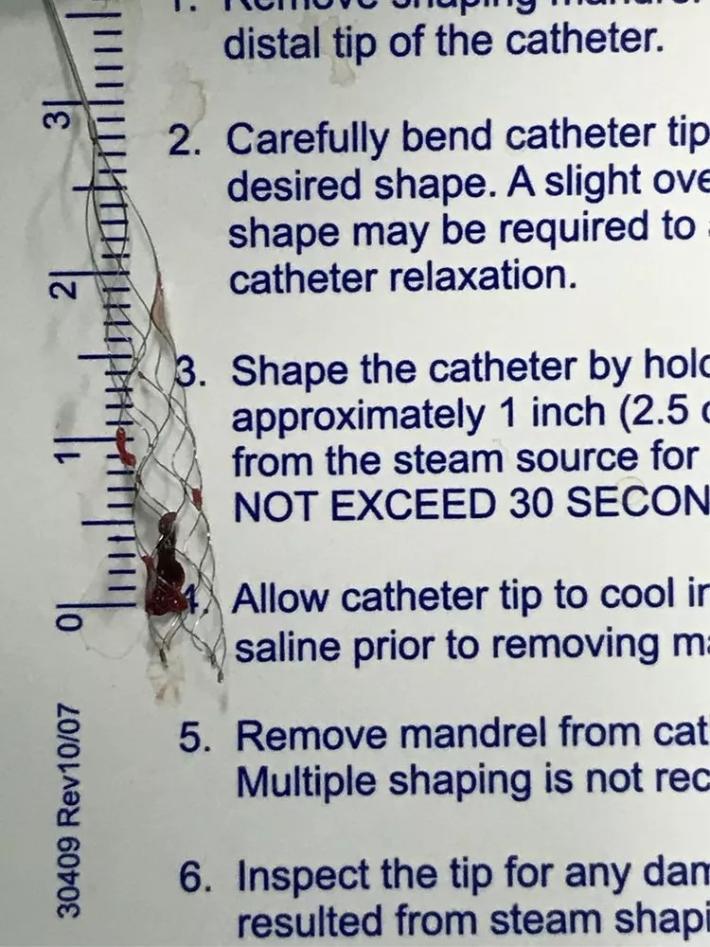

支架和取出来的血栓。